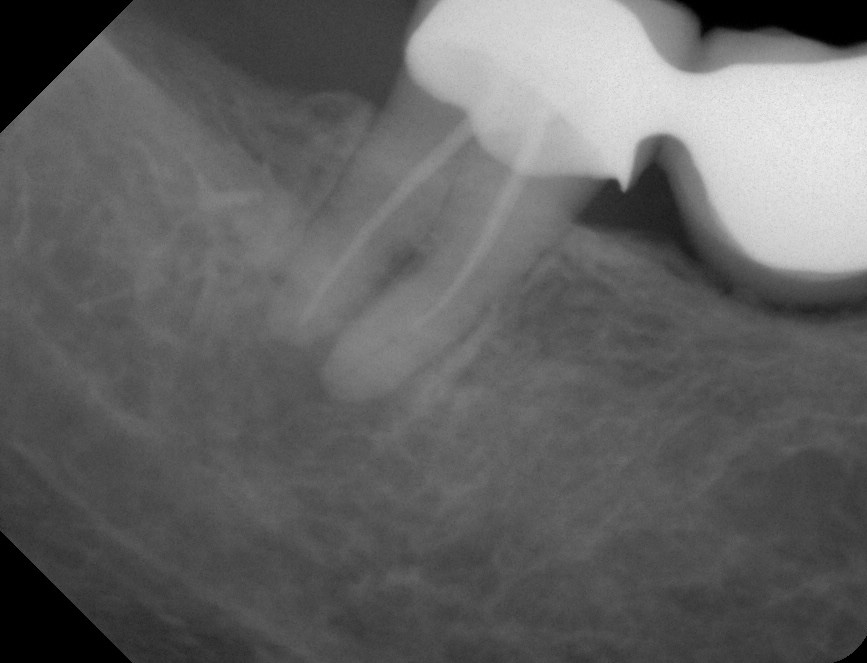

Twee foto’s van een 47 (röntgen en klinisch). Het starten van een wortelkanaalbehandeling is vaak de beste remedie bij acute klachten. FOTO’S: BRAM LAK

Wortelkanaalbehandeling

De richtlijn ‘Endodontische diagnostiek en behandeling’ biedt u op het gebied van de behandeling van acute klachten geen snelle oplossing. Het starten van een wortelkanaalbehandeling is vaak toch de beste remedie. Een goede start van een wortelkanaalbehandeling verdient aandacht en tijd. Mocht u op het moment dat u de patiënt ziet niet de tijd hebben om deze behandeling goed uit te voeren, dan is het voor de patiënt en uzelf beter om die op een later tijdstip te plannen en de patiënt in de tussenliggende periode pijnvrij te houden met adequate pijnstilling. Als alternatief kan er een langwerkend anestheticum (bijvoorbeeld bupivacaïne) toegediend worden. Een te snel en niet zorgvuldig uitgevoerde behandeling is vaak niet effectief en leidt mogelijk zelfs tot meer problemen.